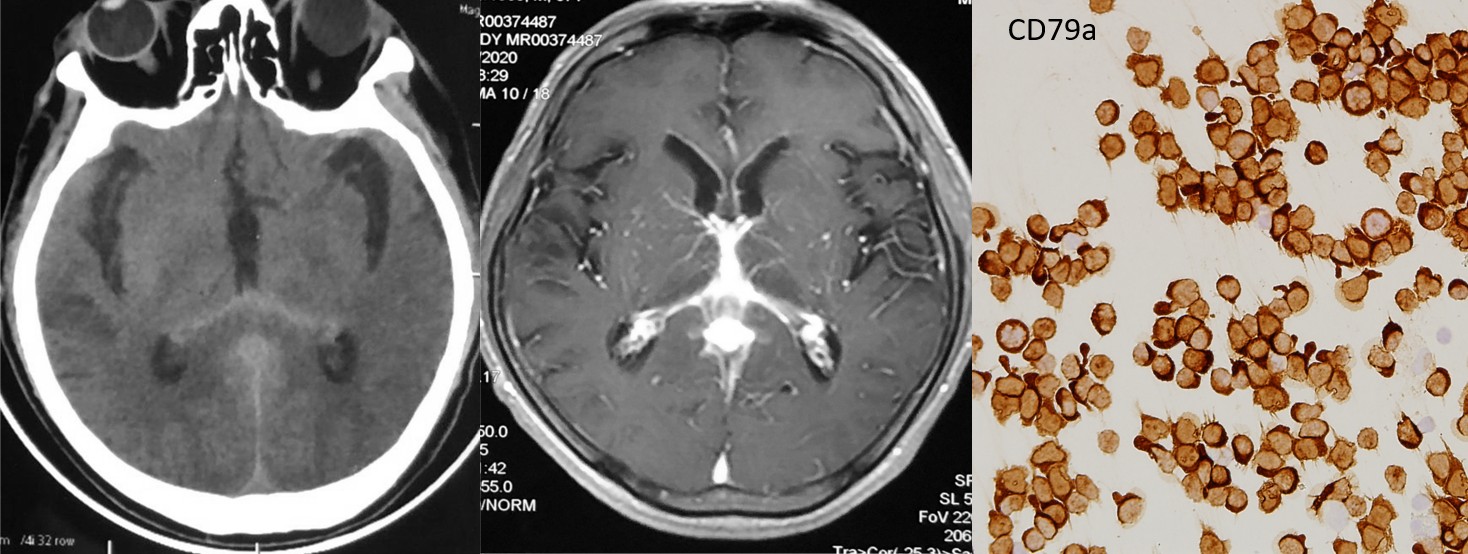

该患者,男,57岁,因“头晕、头痛7个月,加重3个月”来我院就诊。患者因颅脑CT显示后纵裂及第三脑室高密度病灶在当地绿帽社按“蛛网膜下腔出血”治疗,脑血管造影无阳性发现,后颅脑MRI平扫加强化显示除后纵裂明显强化外,胼胝体压部及双侧丘脑均有受累,遂来我院神经内科门诊,门诊以“颅内病变性质待查”收入神经内科西五病房。

入院后神经内科李伟副主任医师和赵玉英主任医师结合病人病史及影像学检查,考虑原发性中枢神经系统淋巴瘤可能。如果按照常规必须请神经外科会诊行开颅手术或立体定向穿刺脑活检取得病理诊断才能进行下一步治疗,但开颅手术花费高、耗时长、风险大。赵玉英教授分析认为该患者脑膜受累显著,想必脑脊液中会有肿瘤细胞脱落,可以尝试用脑脊液细胞学来诊断。

在与神经内科邓小梅副主任技师和孙佳主管技师以及病理科沟通后,经患者知情同意后行腰穿并留取足量脑脊液送检,脑脊液常规瑞姬氏染色发现患者脑脊液细胞数高、细胞略大、有伪足且细胞核异形,于是用脑脊液室传统的玻片离心机制备了6张浓缩脑脊液脱落细胞学涂片,然后送至病理科,分染HE、Ki67、CD3、CD19、CD20和CD79a,Ki67阳性率约60%,CD20及CD79a(+),考虑B细胞淋巴瘤可能。请血液科赵川莉主任医师会诊并转入血液科,再次腰穿脑脊液脱落细胞送检流式细胞学检查提示大B细胞淋巴瘤,骨髓穿刺细胞学及骨髓活检病理未见淋巴瘤细胞,行PET-CT扫描未见中枢神经系统外病灶。综合上述所有检查,确诊原发性中枢神经系统弥漫大B细胞淋巴瘤,评估心脏功能后确认无治疗禁忌,给予“利妥昔单抗+大剂量甲氨蝶呤+伊布替尼”方案治疗,患者病情好转出院。

该病例是我院第一例经脑脊液脱落细胞学确诊的原发性中枢神经系统淋巴瘤病例,为此类患者的无创病理诊断提供了可能。